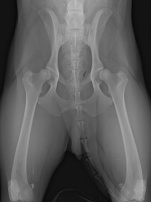

Der Aufbau des Gelenkes entspricht dem eines Kugelgelenkes. Im Becken befindet sich die Gelenkpfanne. In dieser schalenartigen Vertiefung liegt der Gelenkkopf des Oberschenkelknochens. Knorpel in der Gelenkpfanne und auf dem Oberschenkelkopf sorgt für eine reibungslose Beweglichkeit des Gelenkes und hat stoßdämpfende Eigenschaften.

Die Abbildung zeigt die Röntgenaufnahme eines Hundes mit normalen Hüftgelenken.